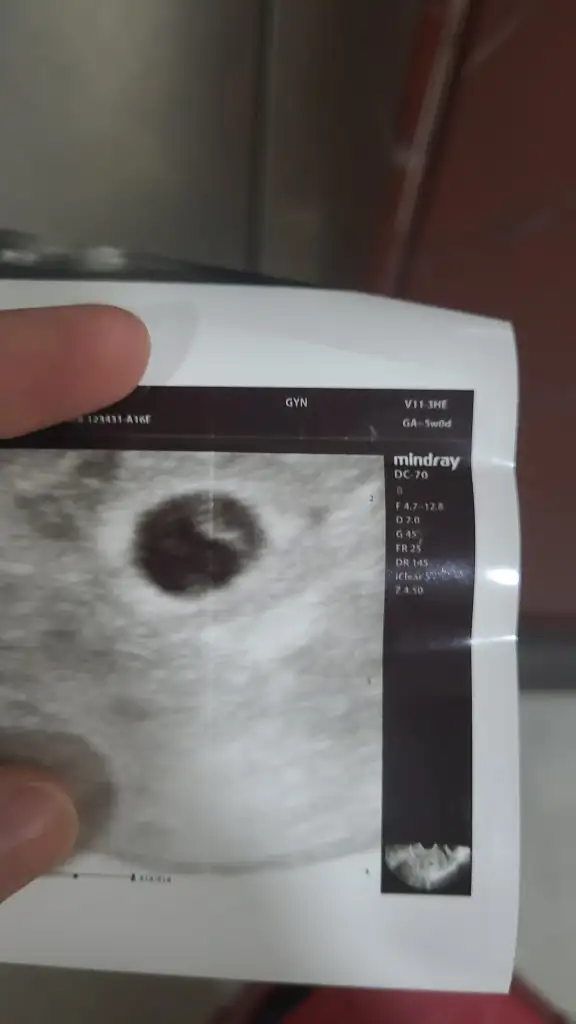

Burdada erkek gibi duruyor bende hamildyim 7haftalij olcak tüm ultrasonlara baktım meraktan benimkine erkek çıkıyor hakkımızda hayırlısı Rabbim gonlumuzdekini gerçekleştirsin inşallahBuda 7 haftalik karindan

Oglunuzda ultrasonda ne taraftaydi aslında böyle şeylere inanmak istemiyorum bakmadanda duramıyorumBuda 7 haftalik karindan

Rabbim gönlünüze göre versin inşallah7 haftalık oglum karından ultrasonda sagdaydı kesem yuvarlaktı bunda ısı 7 haftalık karından solda kesem fasulye gıbı